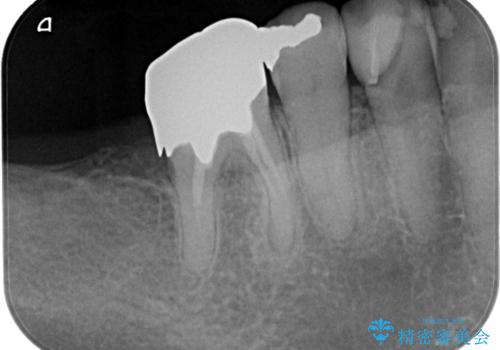

- 治療計画

- 患者様は、右側の奥歯でしっかり噛めないことを主訴に来院されました。診察の結果、右上6・右下6の根管治療が不十分で、感染のリスクがある状態と判断。これらの歯は再根管治療を行い、セラミッククラウンで補綴することにしました。また、右上7・右下7は欠損しており、噛み合わせを回復するためにインプラント治療を計画しました。

まず、右上6・右下6の根管治療を再度行い、根の状態をしっかり整えた上で、セラミッククラウンを装着しました。さらに、欠損していた右上7・右下7にはインプラントを埋入し、セラミッククラウンを装着。治療後は、「奥歯でしっかり噛めるようになり、不安なく食事ができるようになった」と患者様にも大変ご満足いただきました。